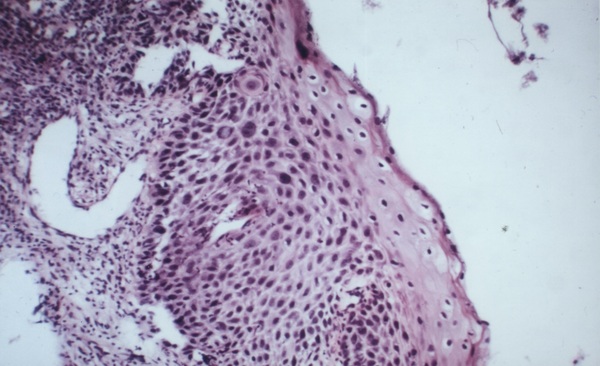

Stem cell niche halo

(see high power: AACR_Scan04.jpg) High-grade intraepithelial neoplasia of uterine cervix (duplicate: DSC_1475.jpg)